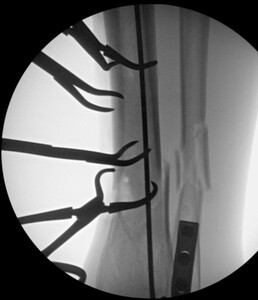

time of transition from a flexed position to semi extended position. This was not dictated by fracture location or type. It is current practice to use the semi extended position in the majority of cases currently. Multiple bone reduction forceps were used to obtain and maintain this reduction. If the fracture was transverse in nature then small drill holes were placed on either side of the fracture and then reduction forceps were used to reduce the fracture. Provisional plates were not used in this series. Please see figures below for radiographs of a representative case. All portions of the case were completed by the treating surgeon as there are few operative assistants available in this clinical setting. The intramedullary nail was then placed though an extraarticular lateral parapatellar approach in a semi extended position (Kubiak, Widmer, and Horwitz 2010) or through a medial parapatellar approach with the knee flexed over a radiolucent triangle. If the fibula was fractured, it was not routinely operatively repaired unless the ankle was found to be unstable. If the ankle was unstable, then the fibula was treated through a separate incision with a plate and screw construct. All wounds were closed in layers with absorbable suture for the fascial layers. Either 0 or 2.0 Vicryl was used in interrupted figure of 8 fashion. All skin incisions were approximated with 3.0 nylon in modified Allgower-Donati fashion (Shannon et al. 2017). All patients were placed into well-padded short leg plaster splint with the foot in neutral dorsiflexion and made non weight bearing until wounds were healed and sutures were removed. At that point all patient were made weight bearing as tolerated on the effected extremity with or without a cast boot as the patient desired.